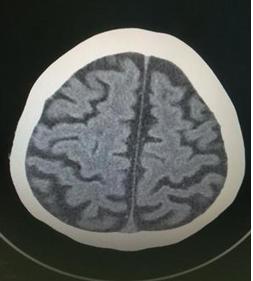

脑萎缩是一种慢性、进行性脑部病变,其病因复杂多样。患有此病的患者主要表现有思维意识障碍、注意力分散、记忆力减退、痴呆等症状。根据病因可将脑萎缩分为生理性和病理性两种。随着年龄的增长,机体功能性衰退,脑细胞功能逐步退化而引起的称为生理性脑萎缩;而由出生缺氧窒息、脑炎、脑出血、脑梗死、脑血管疾病、长期饮酒 ( 酒精中毒 )、一氧化碳中毒、高度营养不良、滥用激素等原因引起的称为病理性脑萎缩。脑萎缩影像学表现为脑室增大,伴有脑沟和脑裂增宽。

脑萎缩CT表现